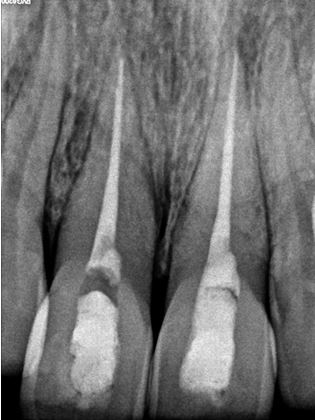

Management of intrinsic discoloration using walking bleach technique in maxillary central incisors

Method. Maxillary central incisors were isolated with rubber dam and root canal treatment was performed. Barrier space preparation was done using a heated instrument. Glass ionomer cement was used a barrier material. Mixture of hydrogen peroxide and sodium perborate was placed in the canal and sealed with intermediate restorative material. After 1 week, the procedure was repeated to achieve the desired results.

Conclusion. Non-vital bleaching is a minimally invasive procedure to restore the esthetics of a discolored non-vital tooth. However, care should be taken to prevent any post-operative complications.